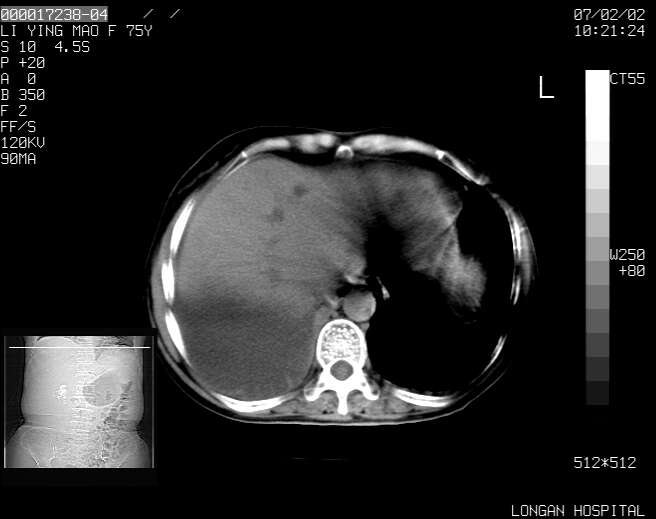

以下是引用dyqct在2007-2-10 8:53:00的发言:[br]考虑:1、肝脏多发囊肿[br] 2、左肾囊肿,右肾多发结石并积水。[br] 3、右胸少量积液。[br] 4、右肾周包裹性积液或淋巴管瘤(有见缝就钻的征象、薄隔、小结节状钙化)?[br] 5、腰椎动脉瘤样骨囊肿?[br] [br] [br]